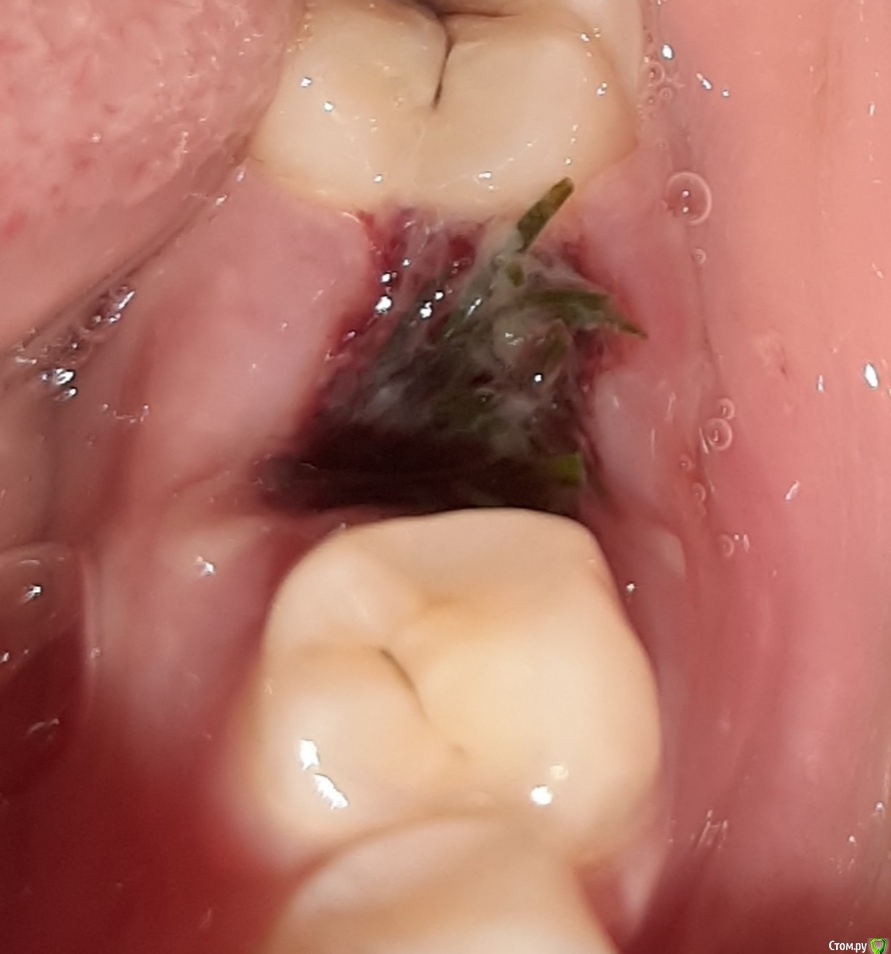

manyasha Опубликовано 4 марта, 2021 Поделиться Опубликовано 4 марта, 2021 сейчас лунка не болит, насчет неприятного запаха не знаю, ибо насморквчера спустя три часа после удаления ела суп что это такое? нужно ли идти к стамотологу? Ссылка на комментарий

АнтонТЛТ Опубликовано 4 марта, 2021 Поделиться Опубликовано 4 марта, 2021 Укроп 1 Ссылка на комментарий

manyasha Опубликовано 4 марта, 2021 Автор Поделиться Опубликовано 4 марта, 2021 (изменено) Укропкак мне его убрать? или в стамотологию идтт что бы мне там убрали? Изменено 4 марта, 2021 пользователем manyasha Ссылка на комментарий

АнтонТЛТ Опубликовано 4 марта, 2021 Поделиться Опубликовано 4 марта, 2021 Поддеть зубочисткой или пинцетом. Не пытаться полоскать. Ссылка на комментарий

manyasha Опубликовано 4 марта, 2021 Автор Поделиться Опубликовано 4 марта, 2021 Поддеть зубочисткой или пинцетом. Не пытаться полоскать.я сейчас слегка попыталась убрать, но оно стало кровить и практически даже не убирается Ссылка на комментарий